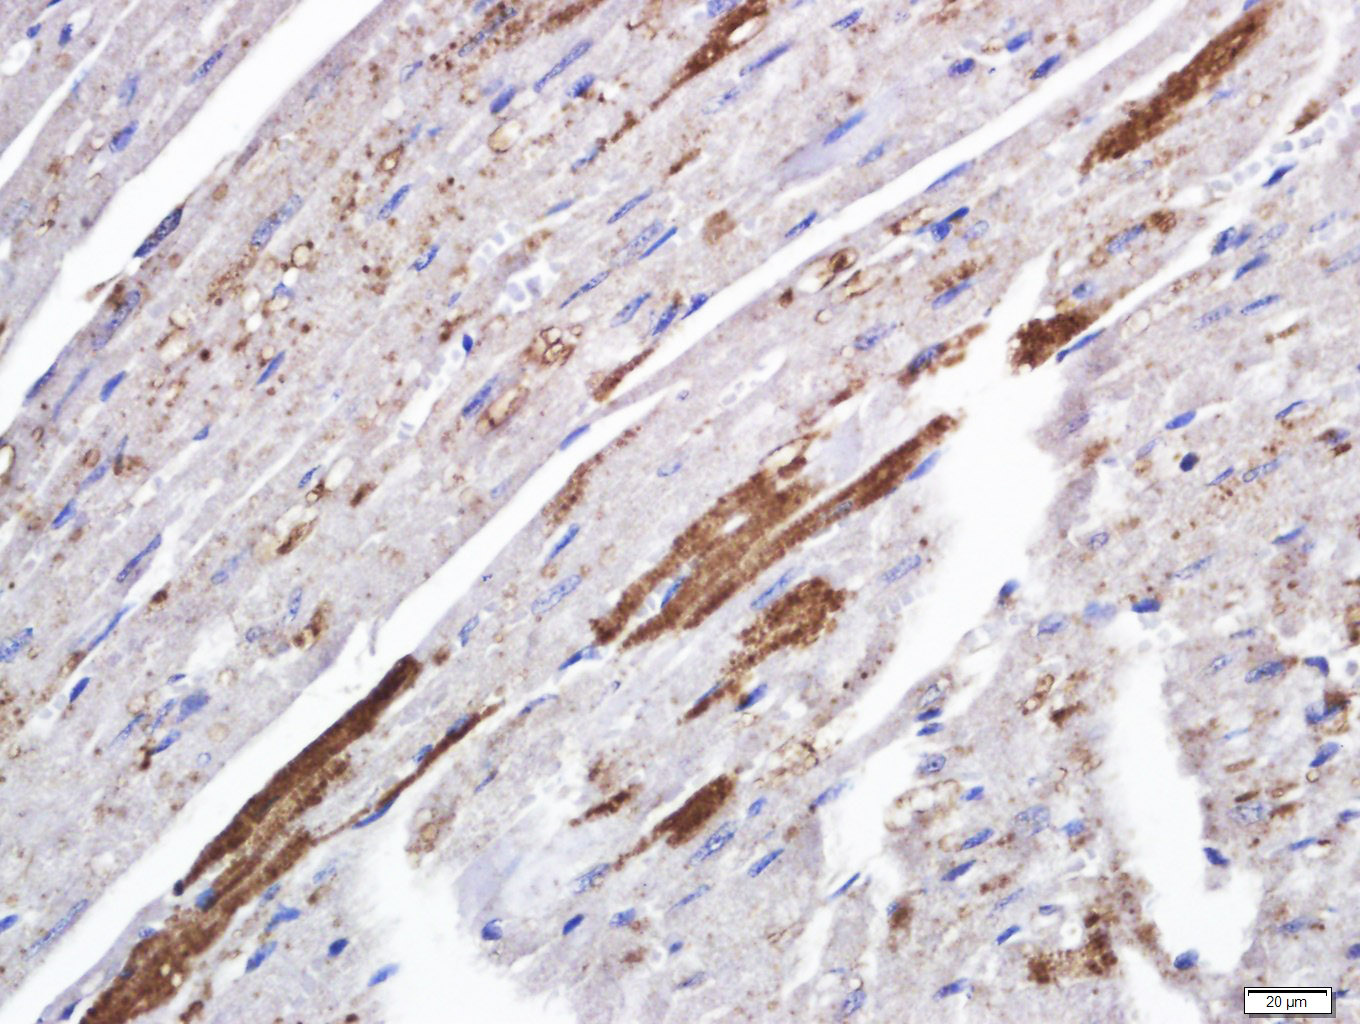

| 英文名称 | TSPAN6 Rabbit pAb |

| 中文名称 | 四分子交联体6抗体(四旋蛋白) |

| 产品应用 | IHC-P=1:100-500, IHC-F=1:100-500, IF=1:100-500 Not yet tested in other applications. |

| 背景资料 | Tetraspanins are a group of hydrophobic membrane proteins that interact with a wide variety of proteins including intracellular signaling molecules, integrins and membrane receptors. Members of the tetraspanin family are characterized by the presence of four hydrophobic domains and play a role in cell development, activation, growth and motility. TSPAN6 (tetraspanin-6), also known as A15 homolog, putative NF-kappa-B-activating protein 321, T245 protein, tetraspanin TM4-D or TM4SF6 (transmembrane 4 superfamily member 6), is a 245 amino acid multi-pass membrane protein that belongs to the tetraspanin (TM4SF) family. TSPAN6 is expressed at high levels in brain, with lower levels of expression found in colon, lung, pancreas, prostate, retina and melanocytes, as well as fetal heart, liver and spleen. The gene encoding TSPAN6 maps to the human X chromosome. |

| {IHC-P} | {1:100-500} |

| {IHC-F} | {1:100-500} |

| {IF} | {1:100-500} |